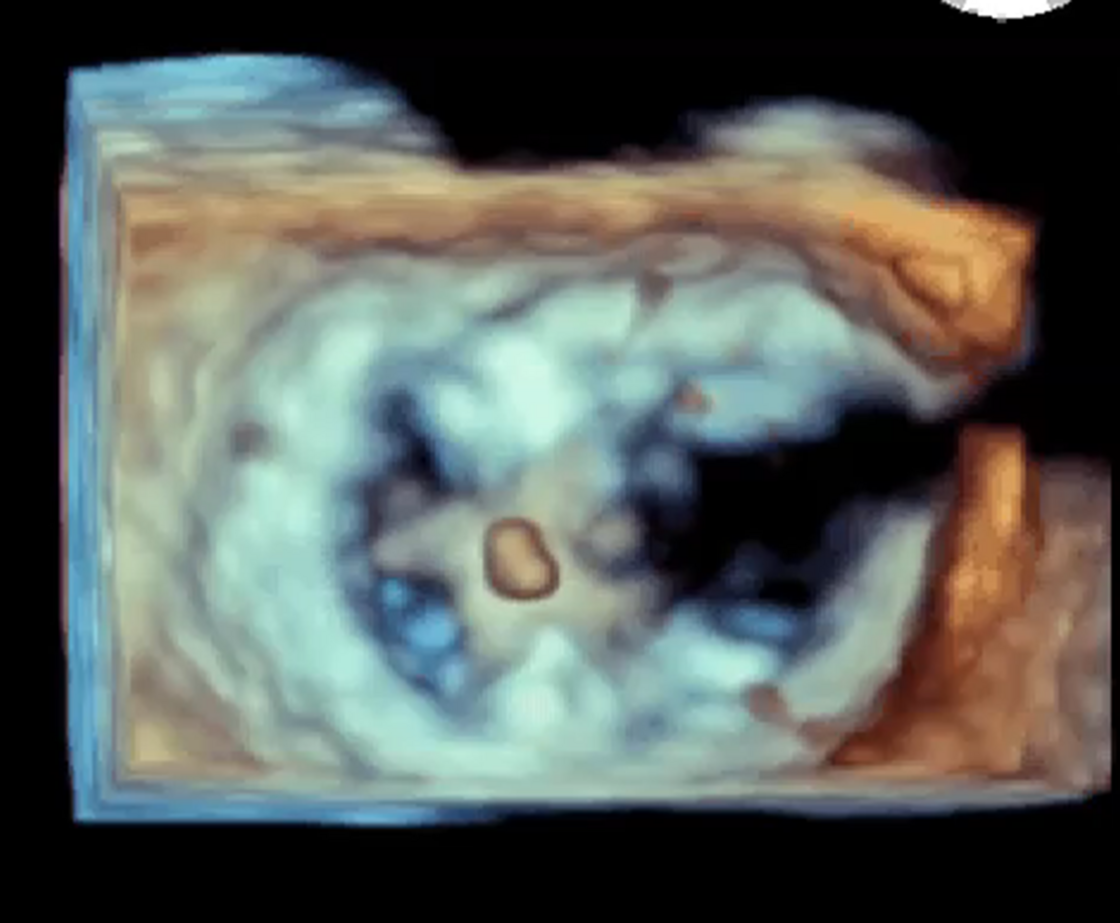

Abbildung 1: Mitralklappeninsuffizienz im anatomischen Modell und Im Ultraschall

Die Mitralklappeninsuffizienz ist eine Undichtigkeit der Mitralklappe. Sie ist der zweithäufigste erworbene Herzklappenfehler nach der Aortenklappenstenose. Die Mitralklappe reguliert den Blutfluss aus dem linken Vorhof des Herzens in die linke Herzkammer. Durch Öffnen der Herzklappe gelangt sauerstoffreiches Blut in die linke Herzkammer und bei Schluss der Klappe wird dieses weiter in den Körperkreislauf zur Versorgung der Organe von der linken Herzkammer gepumpt. Besteht eine Undichtigkeit der Mitralklappe (Mitralklappeninsuffizienz), so schliesst die Klappe nicht vollständig und ein Teil des Blutes fliesst zurück in den linken Vorhof und den Lungenkreislauf. Hierdurch kommt es bei den betroffenen Patienten zu Luftnot (Dyspnoe), Wassereinlagerungen und einer deutlichen Abnahme der Belastbarkeit im Alltag. Auf Dauer geht dies mit einer Schädigung des Herzmuskels einher.